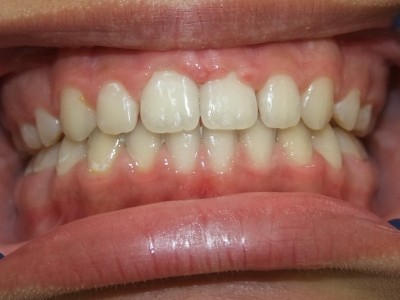

Voor behandeling